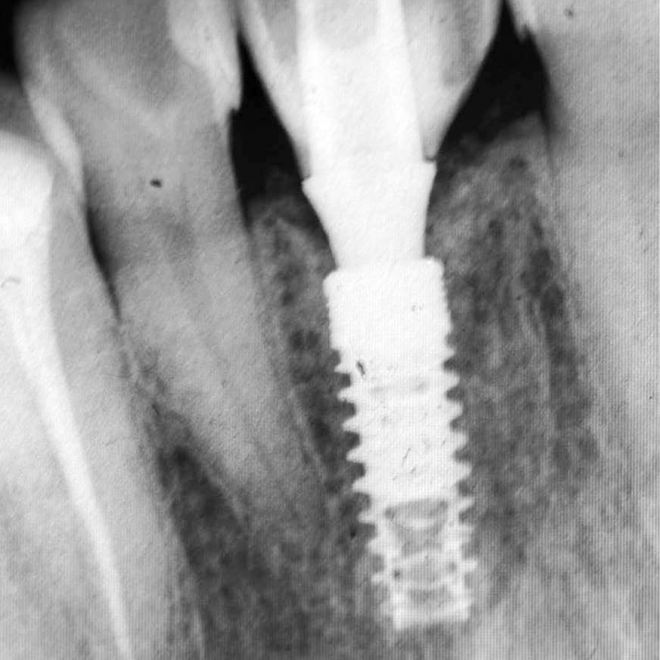

Desde 1985 tenho colaborado com o professor Per-Ingvar Brånemark e nos últimos anos, desenvolvi, juntamente com ele e Christian Brånemark, uma nova macro geometria do ápice do implante. Está parte apical do implante tem a função de reduzir o atrito, devido a seu corte preciso, controlando o torque de inserção, coletando lascas de tecido ósseo para o interior da câmara apical.

“Since 1985 I have been collaborating with professor Per-Ingvar Brånemark and during the last years, I have, together with him and Christian Brånemark, developed a new implant tip.This part of the implant is reducing friction, due to precise cutting, reducing insertion torque and collecting bone chips inside the tip part of”